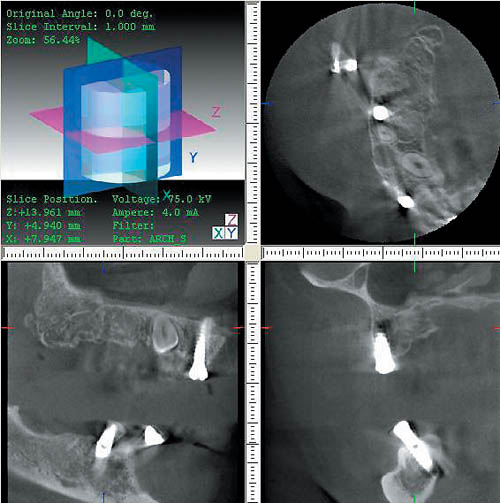

— дает возможность прогнозировать и оценивать отдаленные результаты имплантации и хирургического лечения у пациентов стоматологических клиник (рис. 5);